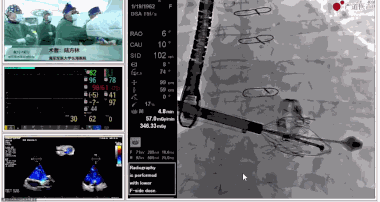

▲瓣膜植入過(guò)程

▲瓣膜植入后釋放的過(guò)程